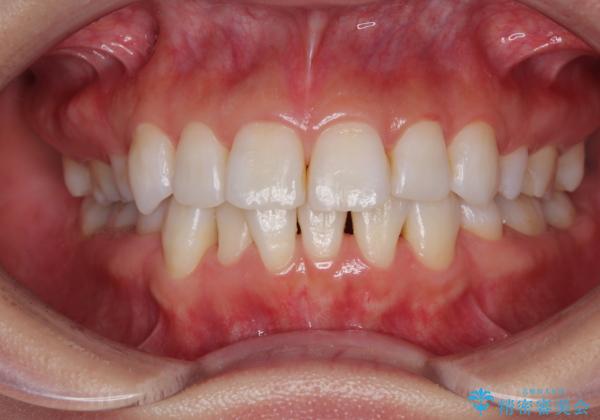

- 上下前歯の後戻りを気にして来院された患者様です。

インビザラインでの治療を希望されていて、デコボコの程度が中等度であり、安価なパッケージにて対応可能と判断されたため、インビザライン・モデレートを用いて矯正治療を行うこととしました。

インビザライン・モデレートは、製作できるアライナーの枚数に制限があるため、移動可能な量に限りがあるものの、インビザライン・ライトよりも枚数が多いため、幅広い症例に対応可能です。